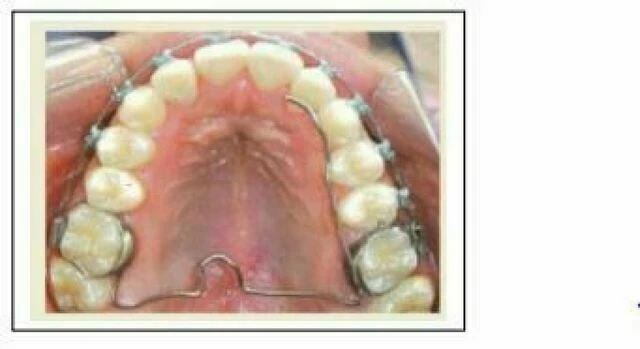

Đây là khí cụ neo chặn hay được sử dụng nhất hiện nay, là kiểu neo chặn được lựa chọn trong những trường hợp có di xa răng cối hàm trên từ trước. Nút Nance gồm có một miếng nhựa nhỏ cỡ đồng xu (đường kính khoảng 1cm), tì lên niêm mạc khẩu cái cứng, ngang mức đỉnh khẩu cái. Nó được làm từ dây SS tròn 0.036”, tựa lên răng cối và trên khẩu cái cứng, xuyên qua miếng nhựa. Khí cụ này có thể dính lên răng cối hoặc hàn vào khâu răng cối (neo chặn cố định) hoặc luồn vào ống gắn bên ngoài răng cối (neo chặn tháo lắp).

2. Cung ngang khẩu (TPA)

Bác sĩ Robert A.Goshgarian đã giới thiệu cung này vào năm 1972. Nó nằm ngang qua khẩu cái như một đơn vị nối cả 2 răng cối thứ nhất với nhau; nó có tác dụng như một khí cụ neo chặn trung bình tạo thành một đơn vị neo chặn kháng lại sự di gần của răng cối và có xu hướng làm xoay chân hàm ếch về phía gần. Đây là một trong những khí cụ neo chặn trung bình đơn giản nhất và hay được sử dụng nhất trong chỉnh nha.

Ta phải lấy dấu sao cho các răng cối trên đó đã được lắp sẵn các khâu dùng để chế tạo cung này, rồi đổ mẫu đã có khâu đặt trong đó, sau đó ta có thể tiếp tục uốn dây SS 0.036” tạo thành cung TPA, khoảng cách giữa dây và niêm mạc khẩu cái là 1- 2mm.

Cung khẩu cái có thể được gắn chặt, hàn vào khâu răng 6 hoặc dán trực tiếp lên mặt trong của răng cối. Nó cũng có thể là khí cụ tháo lắp, bằng cách luồn vào ống mặt lưỡi hàn trên khâu răng cối.